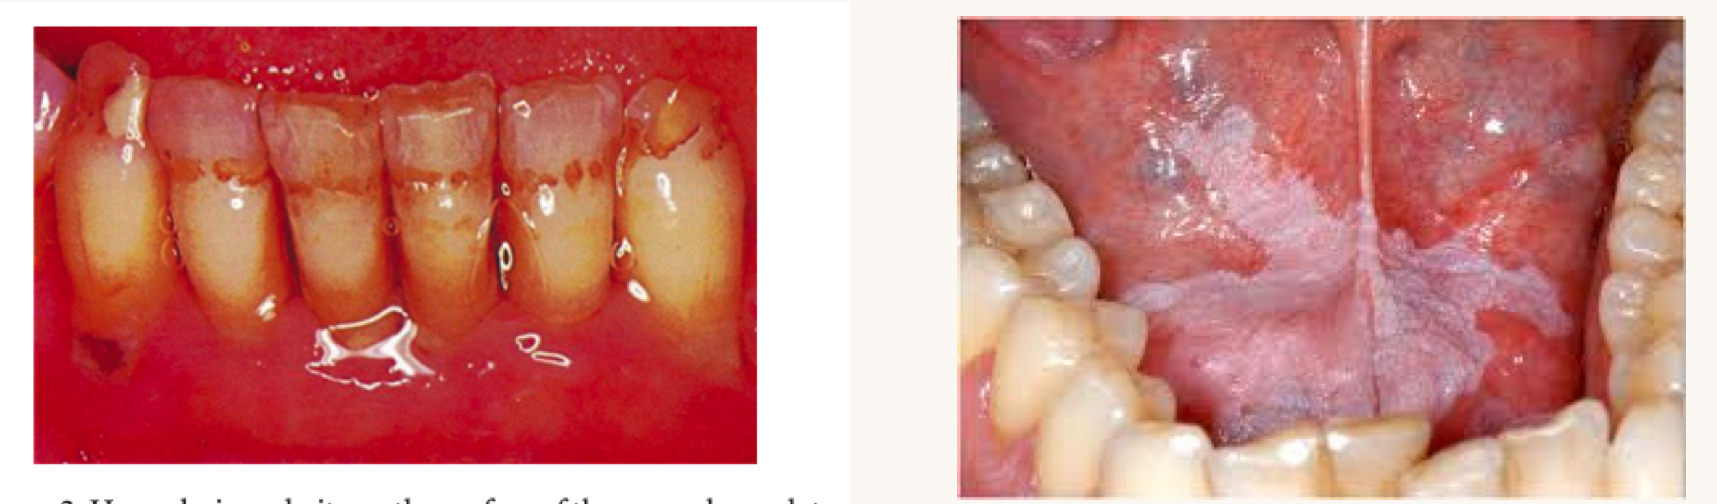

what is this condition and what vitamins is this person likely deficient in?

angular cheilitis

B1, B2, B3, B6

scurvy

vitamin C

manifests as gingival inflammation, petechiae, and poor healing